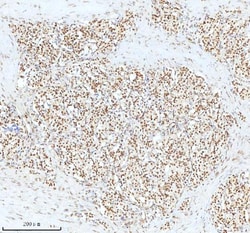

Reconstitute with 0.2 mL of distilled water to yield a concentration of 500 μg/mL. Positive Control - WB: human LNCAP whole cell, human Hela whole cell, human 293T whole cell, human HepG2 whole cell, human Jurkat whole cell, human K562 whole cell, human A549 whole cell, human A431 whole cell. IHC: human bladder cancer tissue, human bladder cancer tissue, human colon adenocarcinoma tissue, human colon adenocarcinoma tissue, human glioblastoma tissue, human glioblastoma tissue, human liver cancer tissue, human liver cancer tissue, human lung adenocarcinoma tissue, human lung adenocarcinoma tissue, human pancreas ductal adenocarcinoma tissue, human pancreas ductal adenocarcinoma tissue, human testicular seminoma tissue, human testicular seminoma tissue. ICC/IF: U2OS cell. Flow: A431 cell. Store at -20°C for one year from date of receipt. After reconstitution, at 4°C for one month. It can also be aliquotted and stored frozen at -20°C for six months. Avoid repeated freeze-thaw cycles.